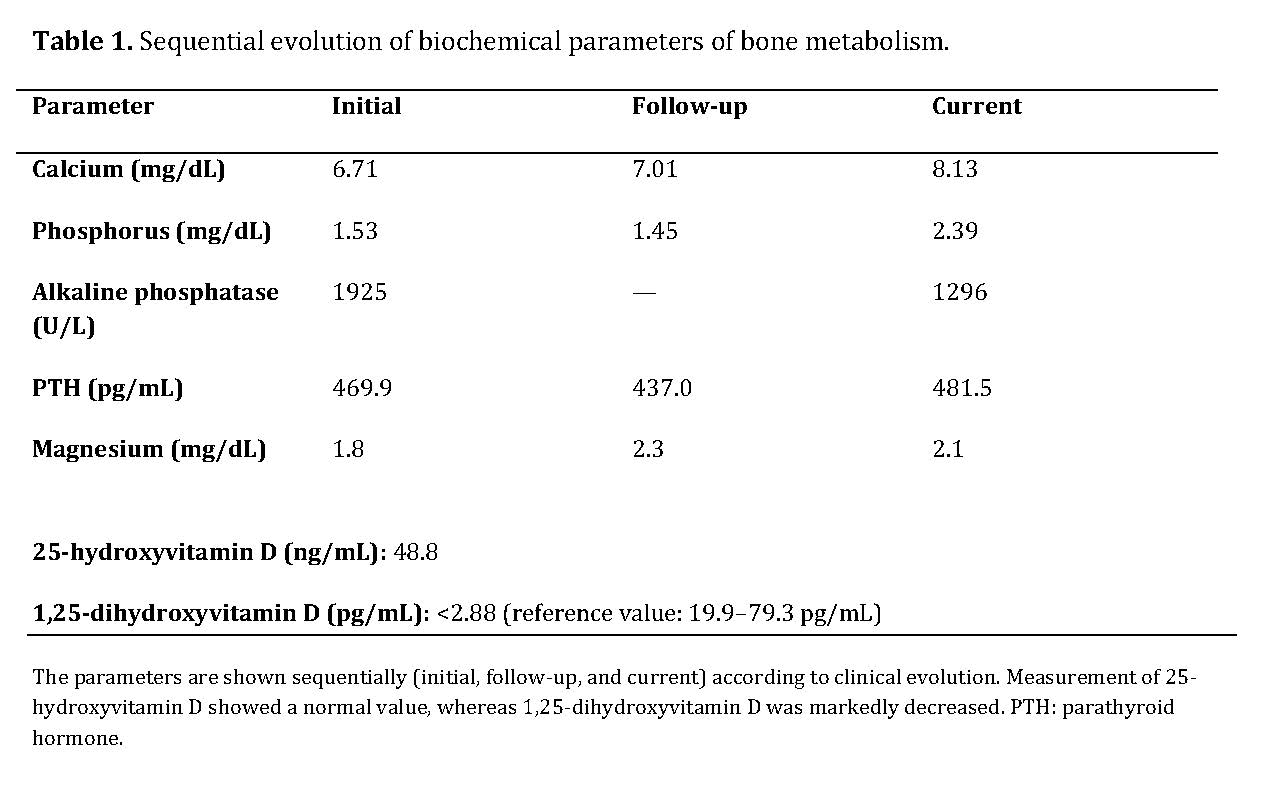

Biochemical studies revealed severe disturbances of mineral metabolism, with persistent hypocalcemia, secondary hyperparathyroidism, markedly elevated alkaline phosphatase, normal levels of 25-hydroxyvitamin D, and a marked decrease in 1,25-dihydroxyvitamin D.

The combination of a calcipenic rickets pattern—characterized by hypocalcemia and hypophosphatemia, severely elevated alkaline phosphatase, and secondary hyperparathyroidism—together with normal 25-hydroxyvitamin D levels and a marked decrease in 1,25-dihydroxyvitamin D is highly suggestive of a defect in vitamin D activation.

The sequential evolution of biochemical parameters is summarized in Table 1, showing persistent hypocalcemia, marked secondary hyperparathyroidism, and a progressive decrease in alkaline phosphatase after initiation of treatment.